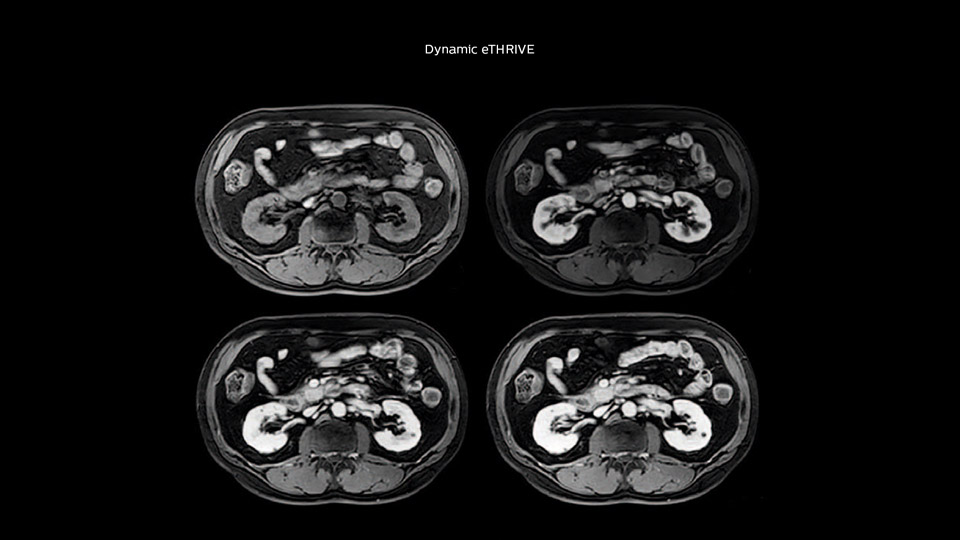

“Our liver exams are quite fast,” says Dr. Baumann. “If the patient tolerates it, we use an arms-up position to reduce the FOV and speed up the exam with dS SENSE.” “We acquire one transversal high resolution T2-weighted sequence with 3 mm slice thickness, for example for pancreas or liver lesions. Then we also add a T2 fat suppressed MultiVane XD SPIR sequence. We perform these two routinely in our liver imaging. We use high dS SENSE factors to significantly shorten scan times to 2-4 minutes, which can improve our protocol; it’s a very robust scan.” “We include mDIXON for the dynamic sequences because of the robust and homogeneous fat suppression we get with that. We had been using eTHRIVE, but we are now quite happy with mDIXON. Sometimes we use a medication to calm the bowels, to further improve the image quality.”